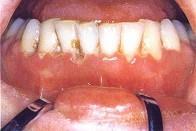

问题 慢性溃疡性坏死性龈炎的主要表现 ( )

选项 A.牙龈水肿 B.游离龈消失 C.附着龈增生 D.牙间乳头消失 E.牙龈增生

答案 D